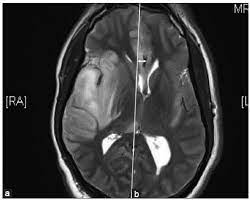

A 40‑year‑old male patient with herpes simplex virus encephalitis presented with altered sensorium. The differential diagnoses include limbic encephalitis (paraneoplastic), gliomatosis cerebri, and status epilepticus. Herpes simplex (hsv) encephalitis is the most common cause of fatal sporadic fulminant necrotizing viral encephalitis and has characteristic imaging findings. Severe edema, petechial hemorrhage, and massive hemorrhagic tissue necrosis can be seen on gross specimens. Two subtypes are recognized which differ in demographics, virus, and pattern of involvement.

Severe edema, petechial hemorrhage, and massive hemorrhagic tissue necrosis can be seen on gross specimens. Two subtypes are recognised which differ in demographics, virus, and pattern of involvement. In the present study, flair bth was most frequently seen in patients with hsv encephalitis. 11 public playlist includes this case Although far less common, essentially any part of the central nervous system can be involved 9. Mri revealed hyperintensities on t2 weighted images in both frontal and temporal lobes suggestive of herpes simplex encephalitis (fig 1). Metabolic, vascular, neoplastic, infective and paraneoplastic diseases. Magnetic resonance imaging (mri) revealed a newly identified enhancing left sphenoid wing meningioma with peritumoral edema in the underlying brain (figure 1).

The characteristic feature of hse is hemorrhagic necrosis of the temporal lobe. Severe edema, petechial hemorrhage, and massive hemorrhagic tissue necrosis can be seen on gross specimens. Because early diagnosis is possible in more cases of herpes simplex encephalitis (hse) as a result of the high sensitivity of mri, now widely available, a larger number of patients are receiving appropriate treatment with iv acyclovir. Herpes simplex encephalitis typically manifests in older adults (about 50% of cases) with headache, fever, altered sensorium, and even seizure. Herpes simplex virus (hsv) is the most common cause of acute fatal sporadic encephalitis, with a particular predilection for the limbic system. that appeared in a recent issue of clinical infectious diseases. It is usually bilateral but asymmetrical. This lesion was seen in all patients as the disease progressed.

It is usually bilateral but asymmetrical. This lesion was seen in all patients as the disease progressed. Two subtypes are recognised which differ in demographics, virus, and pattern of involvement. The lateral temporal lobe and insula are less commonly involved, whereas the basal ganglia, in contrast, are frequently involved, helpful in distinguishing it from hsv encephalitis which characteristically spares the basal ganglia 8. However, mimics of hse, including other infections and increasingly recognized autoimmune causes, have been described in cases of tl encephalitis. Severe edema, petechial hemorrhage, and massive hemorrhagic tissue necrosis can be seen on gross specimens. Because early diagnosis is possible in more cases of herpes simplex encephalitis (hse) as a result of the high sensitivity of mri, now widely available, a larger number of patients are receiving appropriate treatment with iv acyclovir. A feasibility study of quantifying longitudinal brain changes in herpes simplex virus (hsv) encephalitis using magnetic resonance imaging (mri) and stereology. In addition, it was observed in various pathological conditions: Limbic encephalitis, mca ischaemia, tumours, effects of seizures) hyperintense t2 signal in the medial temporal lobes, inferior frontal lobes and insula basal ganglia are usually spared He was managed with intravenous acyclovir 30mg/kg and supportive therapy. We describe the spectrum of etiologies associated with temporal lobe (tl) encephalitis and identify clinical and radiologic features that distinguish herpes simplex encephalitis (hse) from its mimics. Herpes simplex virus (hsv) is the most common cause of acute fatal sporadic encephalitis, with a particular predilection for the limbic system.